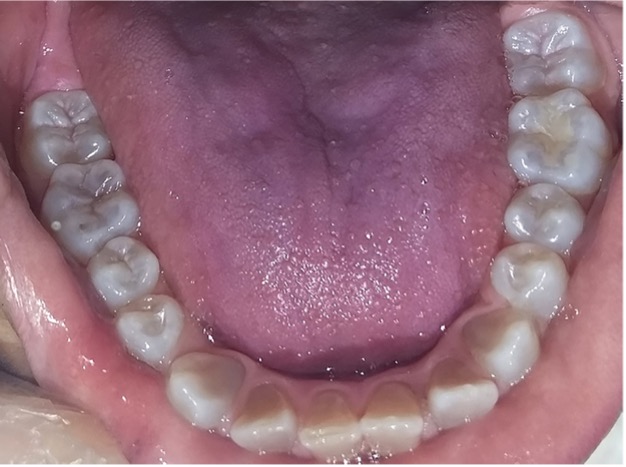

En la radiografía panorámica de control del año 2015 se observó la progresiva obliteración del conducto radicular en el grupo incisivo superior e inferior y en los primeros molares permanentes; presentado los premolares en erupción, un conducto radicular anormalmente amplio en toda su longitud (Figura 8). En la del año 2018 se visualizó la continua aposición de dentina a nivel radicular que obliteró en forma casi total los conductos de la mayoría de las piezas dentarias, a excepción de los segundos molares inferiores (Figura 10).

Figura 10: Rx panorámica 2018.